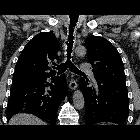

CT

- irregular thickening and nodularity of tracheal cartilage, sparing the posterior (membranous) tracheal wall

- small discrete endophytic nodules (typically ~3-8 mm) may be cartilagenous or calcific (ossified)

- larger nodules may result in luminal narrowing, and should be specifically reported by location and degree of airway narrowing

- diffuse airway narrowing is not typical

- overall appearance is much more irregular compared to benign cartilage calcification